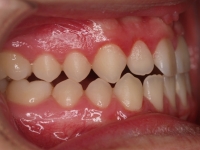

El stripping consiste en la reducción interproximal del esmalte entre los dientes posteriores y anteriores, así obtenemos espacio para alinear los dientes apiñados.

Chica de 17 años tratada en 1 año con stripping en los dientes inferiores